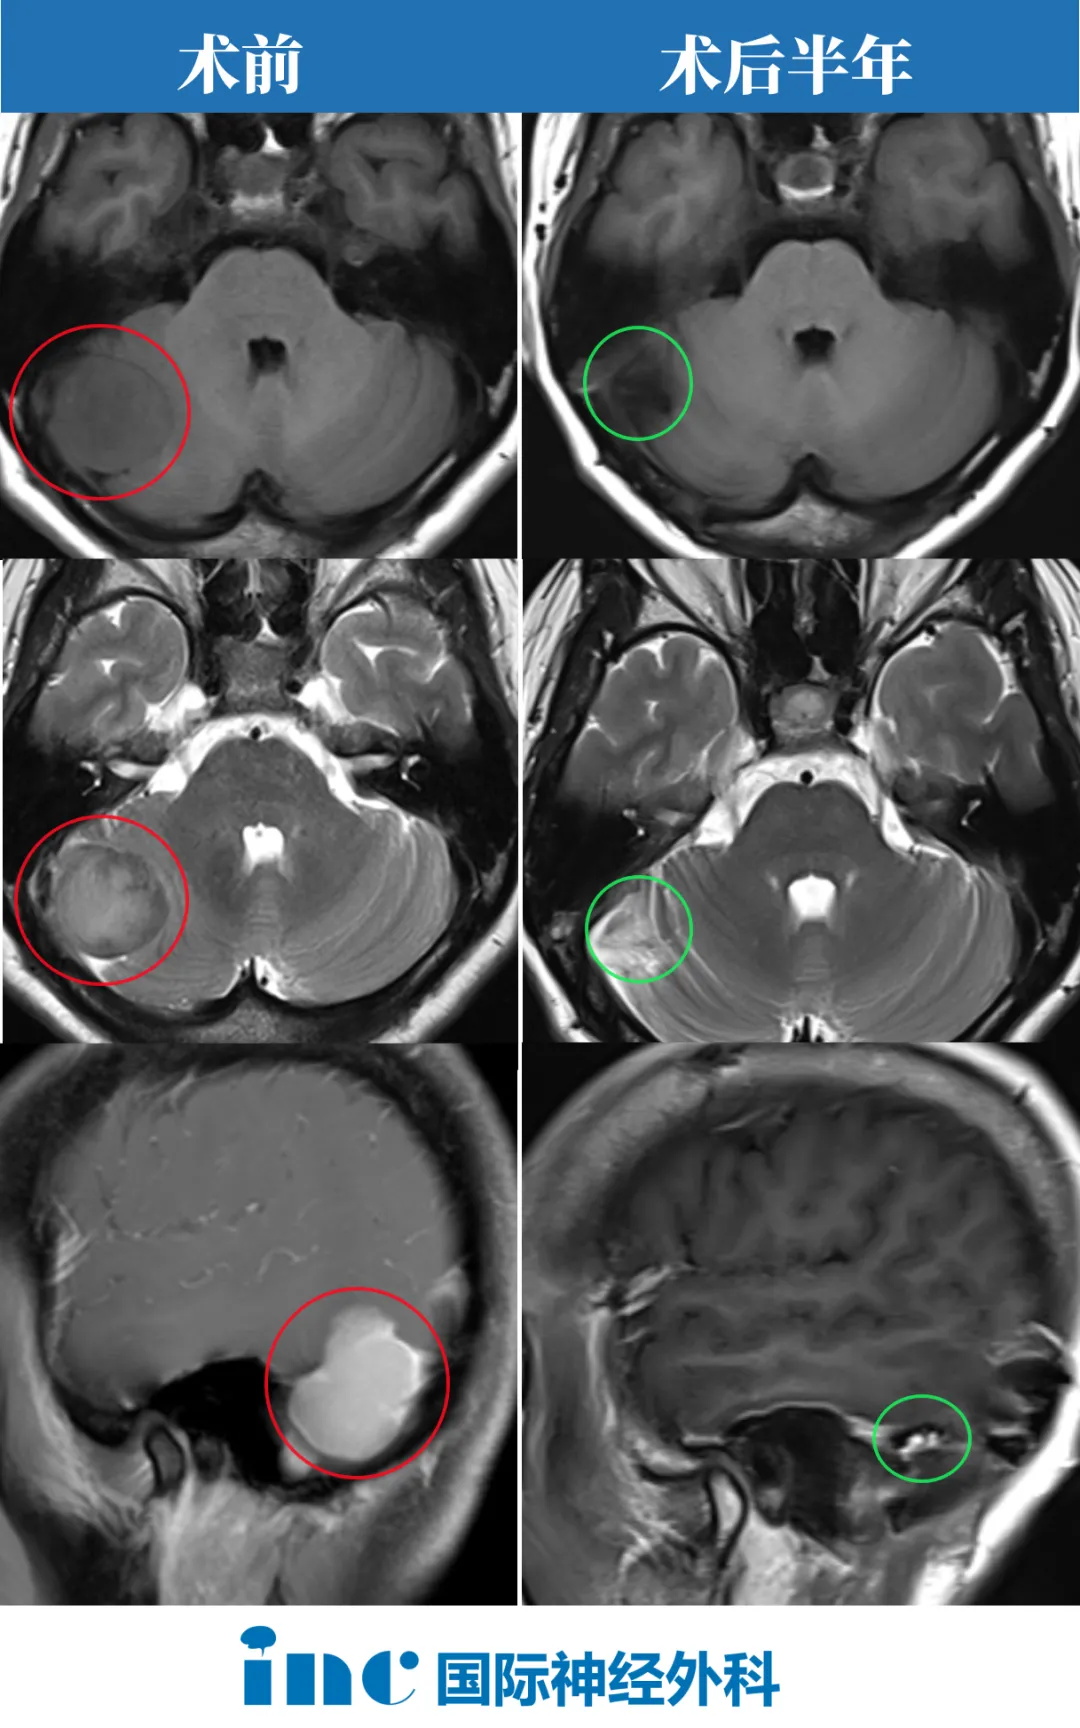

孫女士從體檢發(fā)現(xiàn)腦膜瘤,到成功示范手術(shù),僅18天時(shí)間。手術(shù)過(guò)程順利,腦膜瘤順利全切,無(wú)任何神經(jīng)功能損傷,術(shù)后恢復(fù)好,切口愈合好。術(shù)后病理顯示纖維型腦膜瘤,組織學(xué)級(jí)別CNS WHO 1級(jí)。免疫組化結(jié)果:H3K27me3(+),Ki-67(約2-5%)。

術(shù)后半年隨訪時(shí),巴教授在查看了孫女士影像后回復(fù)

“以下是2024年3月22日的MRI截圖。他們清楚地記錄了腫瘤的完全切除對(duì)大腦或周?chē)Y(jié)構(gòu)沒(méi)有負(fù)面的副作用。周?chē)膶?duì)比增強(qiáng)是由于局部(正常)疤痕形成,剩余的幕也可以看到輕微的增強(qiáng)。腫瘤附著的幕的主要部分被完全切除。這是一個(gè)的術(shù)后情況。腫瘤的完全切除不僅在術(shù)后MRI上可見(jiàn),而且在天壇醫(yī)院的手術(shù)視頻中也有記錄。所以,病人不應(yīng)該擔(dān)心這個(gè)。”